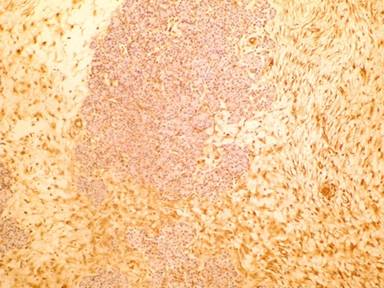

A tumor structure at 665 g weight and 18.5x11x6 cm size that has capsule at outer side has seen on macroscopic evaluation of radical resection specimen. It has seen that outer surface of tumor was smooth and sectional surface yellow and beige color in some areas (Figure 2). Microscopically, tumor infiltration of normal pancreas tissue consists from cells with eosinophilic cytoplasm, which were fusiform with hyperchromatic nucleus, having an undefined cytoplasmic border and encircled at outer part with a thin capsule (Figure 3). Extensive vascular walls were showing hyaline thickening. Hyalinization and myxoid degeneration areas were seen in parts, which were rich hypercellular (tumor rich) and hypocellular (collagen rich). One or two mitotic figure has been encountered in 10 high power fields. Widespread positive staining with vimentin and CD34 has been observed in immunohistochemical staining (Figure 4). It has seen that there was nuclear positive staining with beta-catenin (Figure 5) and focal cytoplasm staining with bcl-2. Negative results have been observed with S100, desmin and keratin. Ki-67 proliferation index has been observed below 2%.

Figure 4. CD34 immunohistochemical staining was positive (20x H&E). |